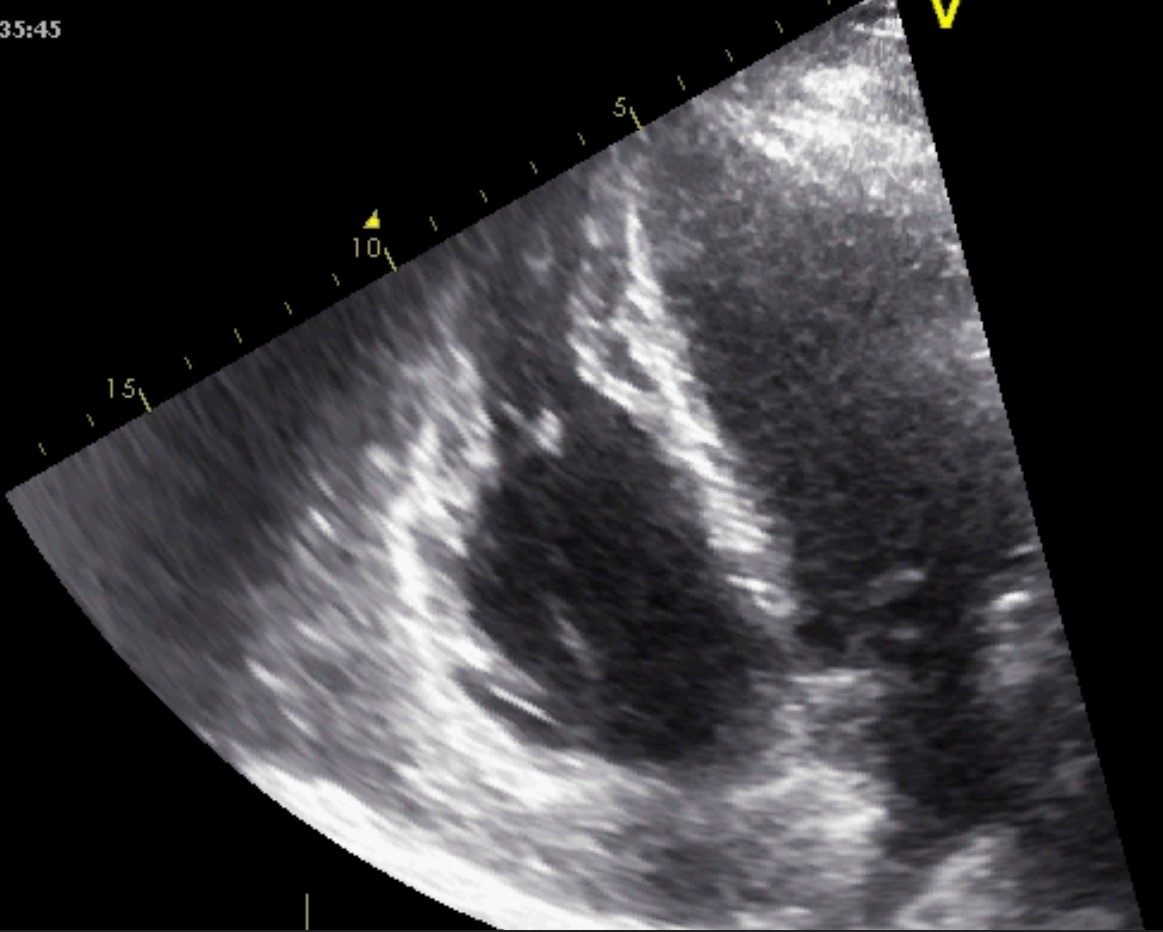

Left ventricular non-compaction cardiomyopathy (LVNC) is characterized by an LV

wall with prominent trabeculae and deep intertrabecular recesses filled with

blood resulting in two layers of myocardium: a thickened noncompacted endocardial

layer and an external, subepicardial thin compacted layer. The diagnosis of LVNC

is obtained through morphologic criteria on transthoracic echocardiography (Fig. 12 and Appendix Video 7). The echocardiographic appearance of isolated LVNC is very

heterogeneous and it can include dilated, hypertrophic or restrictive types. The

Jenni criteria for echocardiographic diagnosis of LVNC are the validated imaging

benchmark [67]. The necessary parameters are assessed using the parasternal

short-axis view at the base, midventricular, and apical levels, and for a

positive diagnosis all four of the following criteria must be met: (1) two

myocardial layers: a thin compacted exterior (epicardial) and a markedly

thickened endocardial layer with several prominent trabeculations and deep

recesses with a maximum ratio of noncompacted to compacted myocardium greater

than 2:1 at end-systole in the parasternal short-axis view; (2) evidence of flow

within the deep intertrabecular recesses through color Doppler; (3) presence of

prominent trabecular meshwork in the LV apex or midventricular segments of the

inferior and lateral wall; (4) maximal systolic compact thickness of

Fig. 12.Echocardiographic non-compaction cardiomyopathy. (A) 2D short axis view, at the level of the apex, showing a meshwork of trabeculae. (B) 2D Apical 4 chamber view showing dilation of the left ventricle, and apical trabeculation. A video of the apical 4 chamber view is available online (Appendix Video 7).